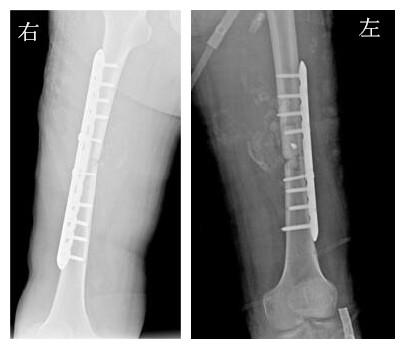

术前诊断:刘某全身多发性陈旧性骨折:左股骨中段开放性粉碎性骨折;右股骨中段闭合性粉碎性骨折;二、重型闭合性颅脑损伤:①左侧颞叶挫伤②左侧基底节区继发性梗塞;三、闭合性胸部损伤:肺挫伤并少量胸腔积液;四、空肠部分切除术后。

▲术前DR 双侧股骨粉碎性骨折